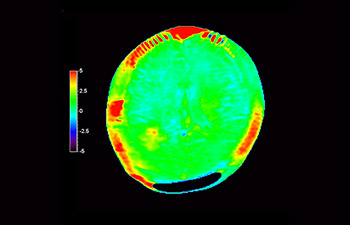

3D APT (Amide Proton Transfer) is a unique, contrast-free, brain MR imaging method addressing the need for more confident diagnosis in neuro oncology. 3D APT uses the presence of endogenous cellular proteins, to produce an MR signal that directly correlates with cell proliferation, a marker of tumoral activity. 3D APT can support trained medical professionals in differentiating low grade from high grade gliomas and, in differentiating tumor progression from treatment effect1.

3D T1w TFE 3D APT